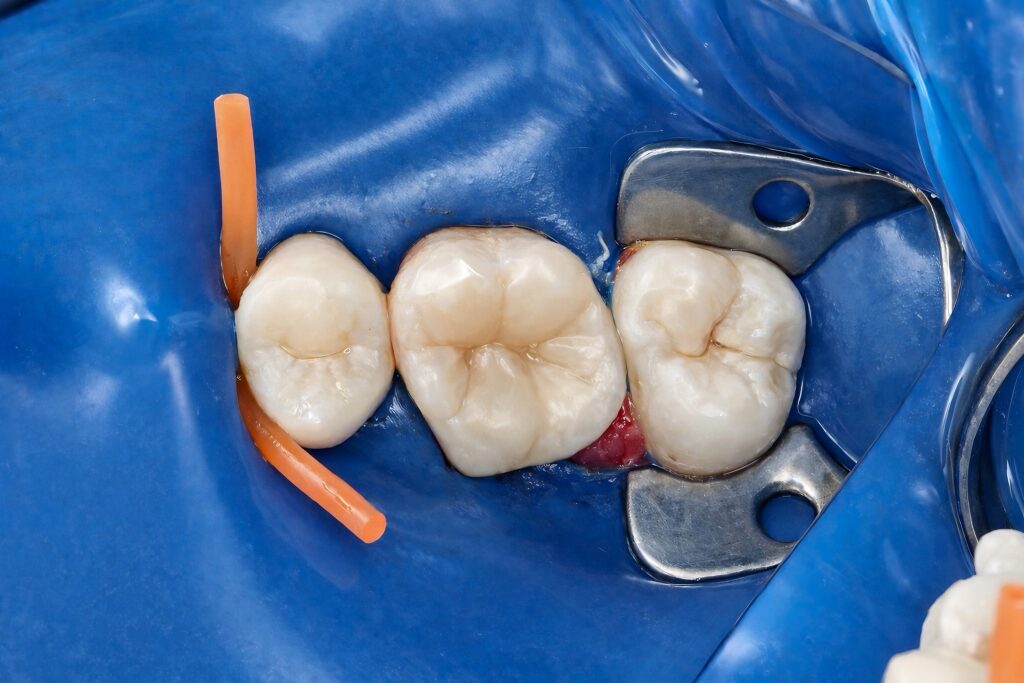

Following endodontic completion, immediate dentin sealing was performed under isolation. Adhesive protocols were selected to maximize bond durability and minimize interfacial degradation.

A biomimetic composite overlay concept was used to restore cuspal integrity. The restoration was built incrementally, respecting natural cusp inclinations, marginal ridge anatomy, and occlusal contacts. This approach allowed:

No unnecessary tooth reduction was performed, maintaining a conservative yet mechanically sound outcome.

Occlusion and Finishing

Occlusion was carefully refined to avoid heavy contacts on weakened cusps. Finishing and polishing focused on smooth margins, anatomical accuracy, and long-term plaque resistance.

The final restoration restored function while maintaining biological respect for the tooth, avoiding the common overtreatment associated with full crowns in similar cases.